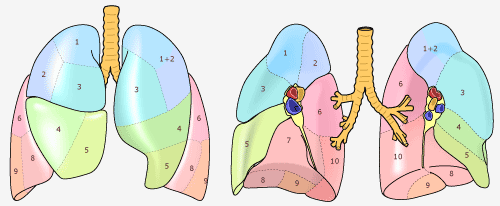

肺は、円錐形の器官で、空気が入っているのでスポンジのような感触の臓器です。肺は胸の左右に存在します。葉(よう)と呼ばれている部分に分かれています。葉とは肝臓、肺、乳腺、脳などの器官の部分を表す用語です。呼吸器系とは、呼吸に関連する器官のことです。これには鼻、喉頭(いんとう)、喉頭(こうとう)、気管、気管支、肺があります。 右肺には3つの葉があり、それぞれ上葉、中葉、下葉といいます。左肺は2つの葉を持っています。上葉、下葉です。右肺は左肺より少し大きいです。

右肺には10個の区域があり、左肺には9個の区域があり、合計で19個の区域です。

右上葉には3個の区域があり、肺の体積を100%とすると、右肺上葉の体積は100%×3/19=16%です。このように計算すると各肺葉の体積は右のようになります。 この値は、絶対的なものではありませんが、肺を切除したときに残りの肺の容量を計算するときに一つの目安になります。